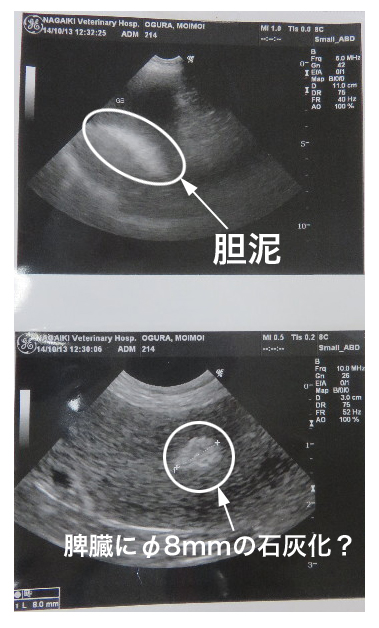

●エコー。

○胆のうにはあいかわらず少量の胆泥が(多くはないそうです。ウルソを飲むことによってなくなることもあるとのこと)

○前回もあった脾臓に石灰化?しているみたいなところ、悪いものではあないとのことです。

直径8mmで経過観察。